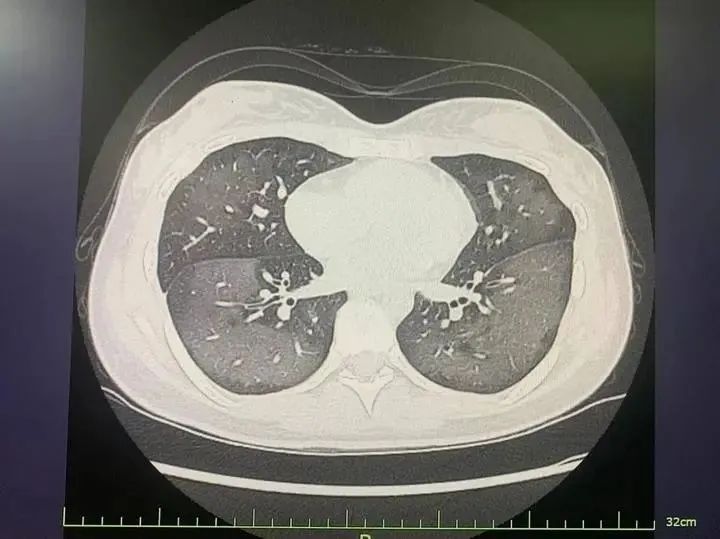

患者肺部CT

经CT检查发现,丽丽的双肺呈现大范围白色样病变,报告提示“白肺”,丽丽被诊断为“急性过敏性肺炎”。

陆远强主任介绍,“白肺”是指在胸部X片或肺部CT等影像学检查中,看到患者肺部呈现大范围的白色阴影。急诊科接诊的“白肺”患者,多见于年龄较大、免疫力低下、有慢性病史或多种疾病共存的人群,年轻人因吸入防晒喷雾变“白肺”的病例并不多见。